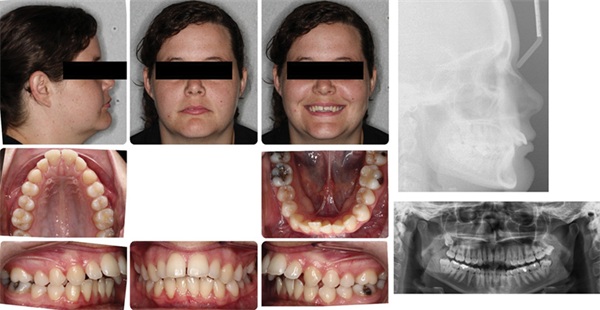

Evaluating the case from “outside-in,” I am satisfied posttreatment with the unique macro/facial features that needed to be controlled. Her pretreatment A-P lip position, which was favored by Nicole and her mom, was well preserved, with only very minimal reduction to her forward position. Additionally, Nicole’s lower one-third facial height slightly increased during this treatment (SN-GoGn and FMA increased by 2 degrees). The eruptive nature of the Class II elastics likely played a role in this (Figs. 7–8).

Also important to consider, Nicole is brachyfacial with well-developed masseters. She has a type of facial pattern that will naturally favor vertical closure with aging. The fact that we have met our aesthetic treatment goals while retaining her full complement of dentition to support the maintenance of her lower one-third facial height is, in my opinion, meaningful. The more she vertically closes over time, the more the dominant unaesthetic feature within her face (chin projection) becomes more dominant and the more “square” her frontal facial form becomes (as opposed to the more natural tapered/ovoid frontal facial shape which is associated with a more balanced lower 1/3 facial height).

Upper incisor labiolingual inclination (U1-SN) decreased from 129 to 107 degrees. It is also important to note that the Class II elastics also advanced her lower incisors significantly, IMPA increased from 89 degrees to 99 degrees.

In addition to considering the quantitative change in the IMPA (“the math”), I would also request consideration of a few “non-math” variables. In my opinion, those would be her facial and smile aesthetics.

Looking at Nicole’s side smiling photo, notice the A-P position of the upper incisors within her smile and within her face (Fig. 9). This is important. Had we retracted her incisors to a greater degree (like we did for Tara by extracting bicuspids), we definitely could have fully reduced the overjet without any lower incisor advancement. In that way the pretreatment IMPA could have been preserved.

But look again at the upper incisor position within her side smiling profile. I would ask what I feel is an important question: Within that face and within that smile, would you aesthetically prefer those upper incisors to be further set back? Should they have been retracted further? Any small bit?

Yes, aesthetics is subjective, but I personally would answer an emphatic no to that question. Within the global aesthetic perspective of her other facial features, I would not at all desire those upper incisors even a half a millimeter more retracted.